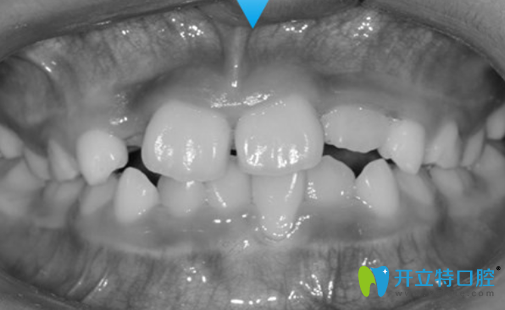

7歲兒子地包天沒有做矯正前樣子:

7歲兒子地包天沒有在成都金琴口腔做矯正前樣子